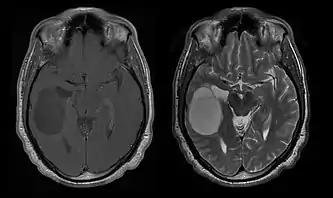

La tomodensitométrie (TDM) et L'imagerie par résonance magnétique (IRM) peuvent détecter efficacement une néoplasie dans le cerveau. L'IRM est plus sensible que la TDM pour identifier les lésions, mais présente des contre- indications pour les patients porteurs de stimulateurs cardiaques, de prothèses incompatibles, de clips métalliques et contre-indications. La TDM reste la méthode de choix pour détecter les calcifications au sein des lésions ou les érosions osseuses de la calotte ou de base du crâne. L'utilisation d' agents de contraste, iodés dans le cas du scanner et paramagnétiques (gadolinium) dans le cas de l'IRM, permet l'acquisition d'informations sur la vascularisation et l'intégrité de la barrière hémato-encéphalique, une meilleure définition de la tumeur tumorale par rapport à l' œdème environnant et à la génération d' hypothèses sur le degré de malignité. L'examen radiologique permet également d'évaluer les effets mécaniques et les modifications importantes des structures cérébrales résultant de la tumeur, telles que l' hydrocéphalie et les hernies, dont les effets peuvent être fatals. Enfin, en préparation à la chirurgie, ce diagnostic peut être utilisé pour déterminer la localisation de la lésion ou l'infiltration de la tumeur dans des zones vitales du cerveau. À cette fin, l'IRM est plus efficace que la tomodensitométrie car elle peut fournir des images en trois dimensions.

Les outils d'imagerie radiologique diagnostique mettent en évidence la modification du tissu néoplasique par rapport au parenchyme cérébral normal (par le biais de modifications de la densité tissulaire imagée électroniquement en TDM et de l'intensité du signal en IRM). Comme la plupart des tissus pathologiques, les tumeurs sont également reconnaissables par une accumulation accrue d'eau intracellulaire. Dans la tomodensitométrie, ils apparaissent hypodenses, c'est-à-dire de moindre densité que le parenchyme cérébral, dans la tomographie par résonance magnétique nucléaire avec relaxation spin-réseau hypointense et en relaxation spin-spin ainsi que l' hypersignal en pondération protonique (PD).

La tomodensitométrie du cerveau montre généralement une masse tissulaire qui peut être améliorée par l'un ou l'autre contraste. Au scanner, les gliomes de bas grade apparaissent généralement isodenses au parenchyme normal et peuvent donc ne pas présenter de rehaussement de contraste. De même, les lésions de la fosse crânienne postérieure sont difficiles à identifier au scanner. Par conséquent, les seuls résultats d'une telle tomographie ne sont pas toujours suffisants à des fins diagnostiques. Dans les cas douteux, l'utilisation de l'imagerie par résonance magnétique plus sensible est indispensable.

Sur-L'IRM montre une tumeur intracrânienne comme une lésion massive qui peut devenir plus luminescente après utilisation du produit de contraste. Cependant, il y a toujours une anomalie de signal dans -L'imagerie par résonance magnétique, qui indique la présence d'une néoplasie ou d'un œdème vasogénique. Habituellement, une luminescence accrue (amélioration du contraste) indique une tumeur d'un grade supérieur de malignité. Un anneau de contraste est caractéristique du glioblastome, avec la partie luminescente correspondant à la partie vitale de la tumeur maligne, et la plus foncée - zone hypointense correspondant à une nécrose tissulaire.